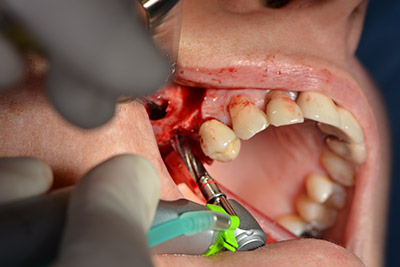

Die anschließenden Bohrungen werden mit einer reduzierten Umdrehungszahl von 300/min durchgeführt. Hier zeigt sich einer der Vorteile der Implantmed. Das chirurgische Protokoll kann voreingestellt werden – die einzelnen Positionen sind über einen einfachen Druck auf die Position „P“ der Fußsteuerung anwählbar. (Abb. 10 bis 11)